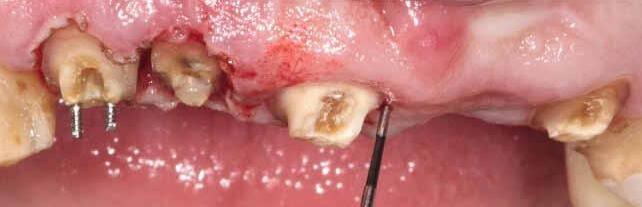

Biodentinee in Bio-Bulk

Fill Procedure

Introduction

Symptomatic teeth that are found to have cracks are one of the more difficult situations for which to plan treatment. Many articles have been published regarding these teeth and unfortunately, there has been no consensus on the best course of treatment. In my experience, it is best to treat these teeth conservatively as this allows for further treatment options if the conservative treatment fails.

Case report by Dr. M. Paul Renner

Clinical signs and symptoms

In 2018, a 59-year-old patient presented with vague pain in the upper left region. He had difficulty locating which tooth was painful, but he reported that he thought it was one of the last two teeth (tooth 26 or 27).

No teeth were tender to percussion. Tooth 26 reacted strongly to cold testing while the other teeth reacted normally. Tooth 26 tested positive to biting on damp gauze but the sensation did not linger. Both tooth 27 and 25 were negative to the bite test. The composite resin restoration in tooth 26 was removed under rubber dam and crack lines could be seen under the restoration (Fig. 1), with the most obvious running from the lingual to the centre of the tooth, and another from the mesiobuccal to the centre. A number of other minor cracks were visible, including one that ran under the buccal cusps (Fig. 1).

a core material for indirect restoration

Fig. 1

These crack lines were discussed with the patient and he was given the option of either restoring the tooth with direct composite resin or with a full- coverage indirect restoration. The patient chose to have the tooth restored with a direct composite resin and so this was performed at this appointment. The patient returned annually for examination and reported the tooth was asymptomatic.

In 2024, the patient presented again with pain in tooth 26. He reported the tooth was very sensitive to cold, with the pain lasting several minutes. He also reported that the tooth had ached spontaneously at times. On examination, the tooth reacted very strongly to cold, which lasted for almost one minute. The tooth was also slightly tender to percussion. The composite resin restoration appeared sound (Fig. 2). A PA radiograph (Fig. 3) revealed no PARL, but the pulp chamber was reduced in size when compared to a previous bite-wing radiograph.

Diagnosis

Given the tooth’s previous history of visible cracks running into the tooth and the current symptoms of moderate to severe pulpitis, a decision was made after discussion with the patient to enter the pulp chamber to assess the condition of the pulp and the depth of the cracks. The plan was to either perform a full pulpotomy or, if no viable pulp tissue was present, extirpate the pulp.

Procedure and treatment

Using local anaesthetic and rubber dam isolation, access was obtained through the composite resin restoration. While the cracks were visible, they appeared similar to the image from 2018 (Fig. 4). The roof of the pulp chamber was removed and vital tissue was found, which did not appear to be heavily inflamed (Fig. 5). A pulp stone was also present (Fig. 6). Removing this revealed bleeding pulp tissue at the opening of the root canals. A cotton pellet soaked in NaOCl was placed on the pulp tissue at the opening of the root canal and after five minutes the bleeding had ceased (Figs. 7 and 8).

As the plan was to restore the tooth with a full- coverage indirect restoration, the entire pulp cavity was filled with Biodentinee™ with the Bio-Bulk Fill technique. (Fig. 9).

The patient returned after twelve weeks and reported that the tooth had been asymptomatic (Fig. 10). At this appointment, a preparation for a ¾ crown was performed (Fig. 11). The Biodentinee™ was left in situ, cut back and used as a core for the restoration. A PVS impression was recorded, and a BISAcrylic temporary crown cemented with provisional cement (Fig. 12).

Three weeks later, a monolithic zirconia crown (Fig. 13) was bonded onto the tooth (Fig. 14). The tooth will be monitored and a review radiograph taken after six months.

Fig. 2: Pre-op composite resin restoration, 2024.

Fig. 5: Initial exposure of the pulp chamber showing slight bleeding and pulp stone.

Fig. 3: PA radiograph.

Fig. 6: Pulp stone removed.

Fig. 8: Palatal root opening with vital tissue after bleeding has stopped.

Fig. 4: Initial access showing existing cracks.

Fig. 10: Tooth at 12-week review.

Fig. 7: Buccal root openings with vital tissue after bleeding has stopped.

Fig. 9: Cavity filled with Biodentinee™.

Discussion

This case highlights a number of elements of pulpotomies in teeth with cracks. Firstly, many teeth with deep cracks have a long-standing mild pulpitis, to which the pulp has responded by producing reparative dentinee that often appears in the form of a pulp calcification. The operator must be careful when performing vital pulp therapy on these teeth as it is often difficult to differentiate the pulp calcification from the floor of the pulp chamber.

Any pulp calcifications must be removed before assessing the condition of the radicular pulp tissue.

Secondly, in teeth with pulp symptoms resulting from cracks, it is best to perform a coronal pulpotomy. This allows the floor of the pulp chamber to be examined for any extension of the crack across the floor, which would greatly reduce the prognosis for the tooth.

Conclusion

The ability to use Biodentinee™ in the Bio-Bulk Fill technique has a number of advantages in cases like the above.

The initial vital pulp therapy appointment can be shortened by completely filling the cavity and using the Biodentinee™ as a permanent dentine replacement and an interim enamel replacement. The fact that the material can be left for up to six months allows time to assess the success of the procedure before committing to the final indirect restoration. The strength of Biodentinee™ means there is no requirement to place a separate core material.